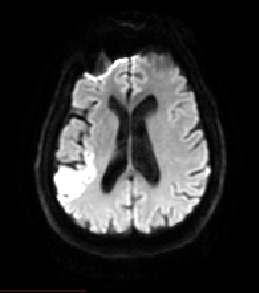

La première série d'images (2 heures post-AIC) montre un AIC sylvien gauche, avec occlusion de l'artère sylvienne apparaissant sur l'ARM (voir illustration ci-dessous). Une première image, acquise en pondération T2*, ne permet pas de révéler l'AIC. Une seconde image réalisée en IRM de diffusion met en évidence l'AIC au stade aigü (hypersignal enregistré dans l'hémisphère gauche au niveau de la lésion). Suite à cet examen, le patient subit un traitement thrombolytique.

Coupe axiale, IRM de diffusion |

- IRMsujet12212anatpathologieAVC_dwi_2H.img : IRM de diffusion acquise 2heures post-AIC. L'AIC est détecté par la présence d'un hypersignal au niveau du lobe pariétal gauche. Cette image est exploitable uniquement dans le plan axial du fait d'un trop faible nombre de coupes dans les autres plans. Caractéristiques techniques : FOV : 256, 50 coupes ; résolution spatiale : 1,09 X 1,09 X 5,5mm3 ; TR : 7000ms ; TE : 60,7ms ; Flip angle : 90°